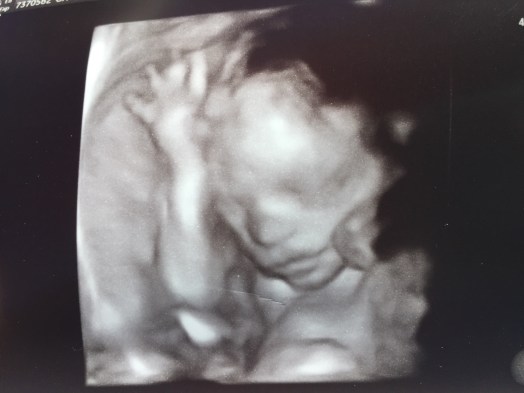

At 25 weeks we got another ultrasound done. Baby S wasn’t cooperating at the 20 week ultrasound but he/she cooperated this time! We got to see a 3D image of the heart; probably one of the coolest things I’ve ever seen! Technology is amazing! They said they can detect like 85% of heart defects with those ultrasounds. Obviously they can’t detect everything, but they can see so much with those scans. Everything looks great which makes us both breathe a sigh of relief!

And can you believe that this was our

‘little embryo that could’ 23 weeks ago? ~~~~~>

Yep, one of those little puffs of air that was holding our embryo to its new ‘womb sweet womb.’ And now — that little embie has a button nose, eyes, lips, arms, legs, brain, heart pumping…etc etc. WOW. Just so much amazing-ness I can’t even wrap my mind around it. This truly is what miracles are made of!